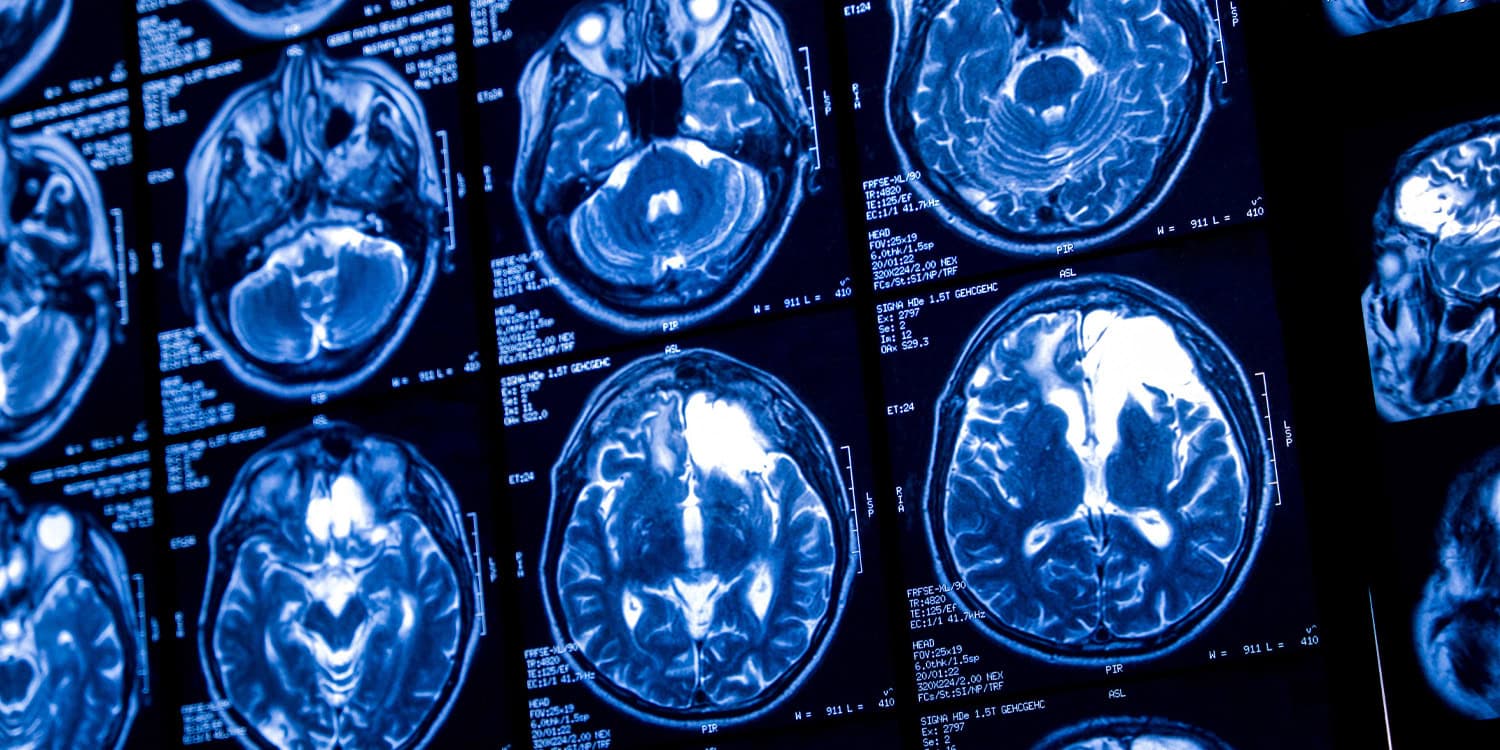

A recent study published in the journal Alcohol provides evidence that even low-level drinking may have negative consequences for brain health over a person’s lifespan. The findings suggest that the total amount of alcohol consumed…